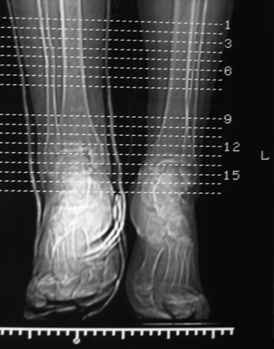

Огромное спасибо всем, кто участвует в обсуждении случая! Приношу глубочайшие извинения и участникам дискуссии и тем, чье внимание просто отвлек своим сообщением. В цейтноте получилось так, что на форум, необоснованно, отправил свои предварительные соображения. Хронология событий следующая. Пришла больная, на руках тот снимок в гипсе, который я выложил. Рассказала, что в 1999г. ломала на этой-же голени обе кости в средней 1/3. Травма тоже была неадекватно низкоэнергетическая - стояла на остановке, шагнула, оступилась - оскольчатые переломы обеих костей. Пластина на большеберцовую. Сросталось долго, линии перелома прослеживались на протяжении 5 лет. Теперешний перелом после того как оступилась в квартире.

Посмотрели снимки после репозиции - не понравилась зона синдесмоза.

Сделали 3/4-е - впечатление, что в 99-том там что-то было. На

5.11.09г. запланирована КТ.